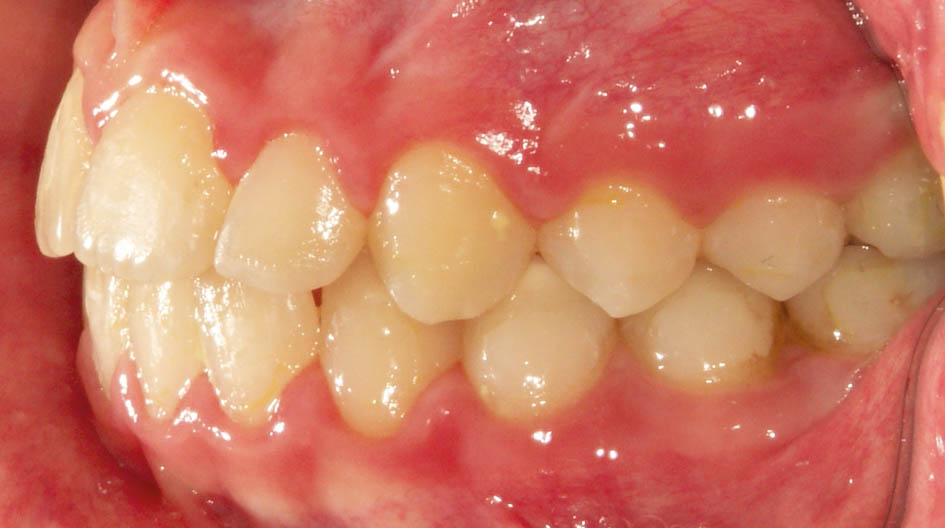

بعضی موقع چند مشکل را با هم در یک کودک میبینید. مثلاً بیمار کراس خلفی یک طرفه و کراس قدامی (شکل 36-5 و 37-5) دارد.

شکل 36-5: کراس بایت خلفی در سمت چپ

شکل 37-5: سمت راست کراس بایت خلفی ندارد پس کودک کراس بایت خلفی یک طرفه دارد.

از آنجایی که دندانهای خلفی بالا تیلت پالاتالی ندارند(شکل38-5) و میدلاین دندانی و چانه بیمار (شکل39-5 و40-5) به چپ منحرف است به کراس دو طرفه و انحراف طرفی مندیبل پی میبریم.